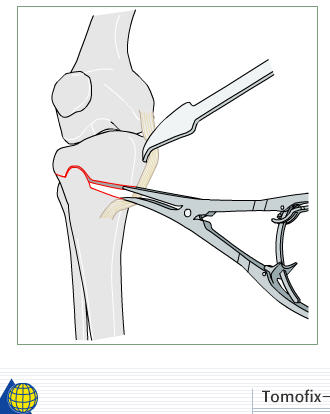

I prefer a medial opening wedge. Currently I prefer the tomofix system by synthes. Its instrumentation allows "dialing in" the correction nicely, and the fixed angle construct provides excellent stability. A few other companies have similar systems, Arthrex for example. Trying to hinge the correction on intact lateral cortex (1 cm.) is key to preserve stability.

The nonunion/hardware failure rate is substantially higher when the lateral cortex is breeched. Fibular osteotomy not required.

Attached is a screen capture from the AO foundation website which has an excellent training module on performing an opening wedge HTO. It shows from preop planning to intra-op techniques. It is helpful even if you don't use their product to perform the procedure. Certainly it is not mandatory to use any osteotomy system to obtain and secure a well done osteotomy - im not sure what instrumentation you have access to.

The question of what to fill the opening wedge with is an issue. Illiac crest is the gold standard, but has its own morbidity, and doesn't add to the overall cosmesis desired by this young lady. You may consider allograft or other substitutes, but research done at my center shows moderate increased likelihood of construct failure.